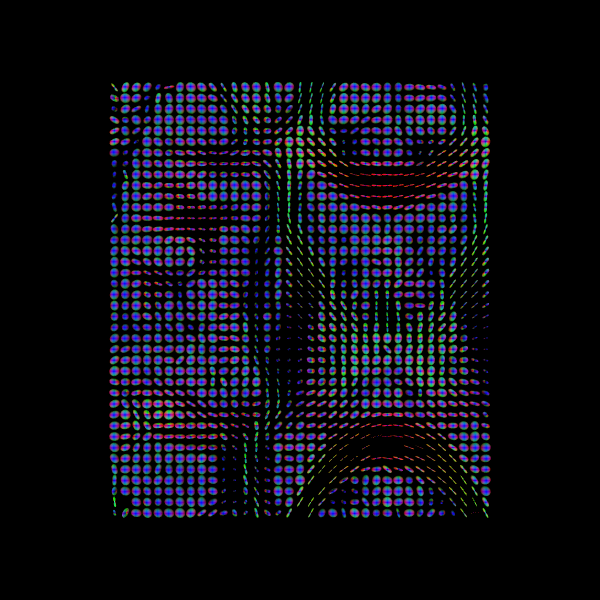

2025-12-22 09:10:44 | INFO | nipype.workflow | [Node] Cached "_tpms_std2t1w1" - collecting precomputed outputs

2025-12-22 09:10:44 | INFO | nipype.workflow | [Node] "_tpms_std2t1w1" found cached.

2025-12-22 09:10:44 | INFO | nipype.workflow | [Node] Cached "_averages0" - collecting precomputed outputs

2025-12-22 09:10:44 | INFO | nipype.workflow | [Node] "_averages0" found cached.